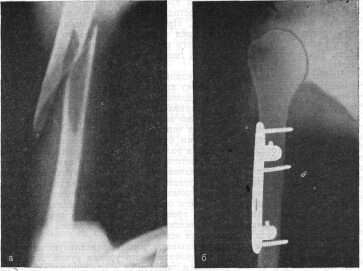

Здравствуйте. Вы не указали, какое лечение получала ваша жена в течение этих 40 дней после травмы. Обычно после изучения рентгеновских снимков в 2-х проекциях врач назначает или скелетное вытяжение, или осуществляет репозицию.

Он сопоставляет костные фрагменты, чтобы еще больше не повредились нервы и кровеносные сосуды, связки и мышечная ткань. Репозиция проводится закрытым или открытым методом.

После успешного сопоставления накладывают лонгету или гипсовую повязку. Чаще всего накладывают торакобронхиальную гипсовую повязку и назначают УВЧ для активизации кровотока для доставки питания и кислорода к месту перелома, венозного и лимфооттока.

Если осколков много, то применяют открытую репозицию. Хирург-травматолог может поставить платину с винтами и стержни. Если имеются очень маленькие фрагменты костной ткани – 4 и более, которые невозможно сложить, их удаляют.

Затем назначают лечение, дают обезболивающие препараты, и делают контрольные снимки, чтобы выяснить, насколько сформировалась и окрепла костная мозоль, нет ли повторного смещения, какое состояние у нервов, сосудов и соединительной ткани. Если сосуды и нервы были повреждены, то во время открытой репозиции на них должны были наложить швы.